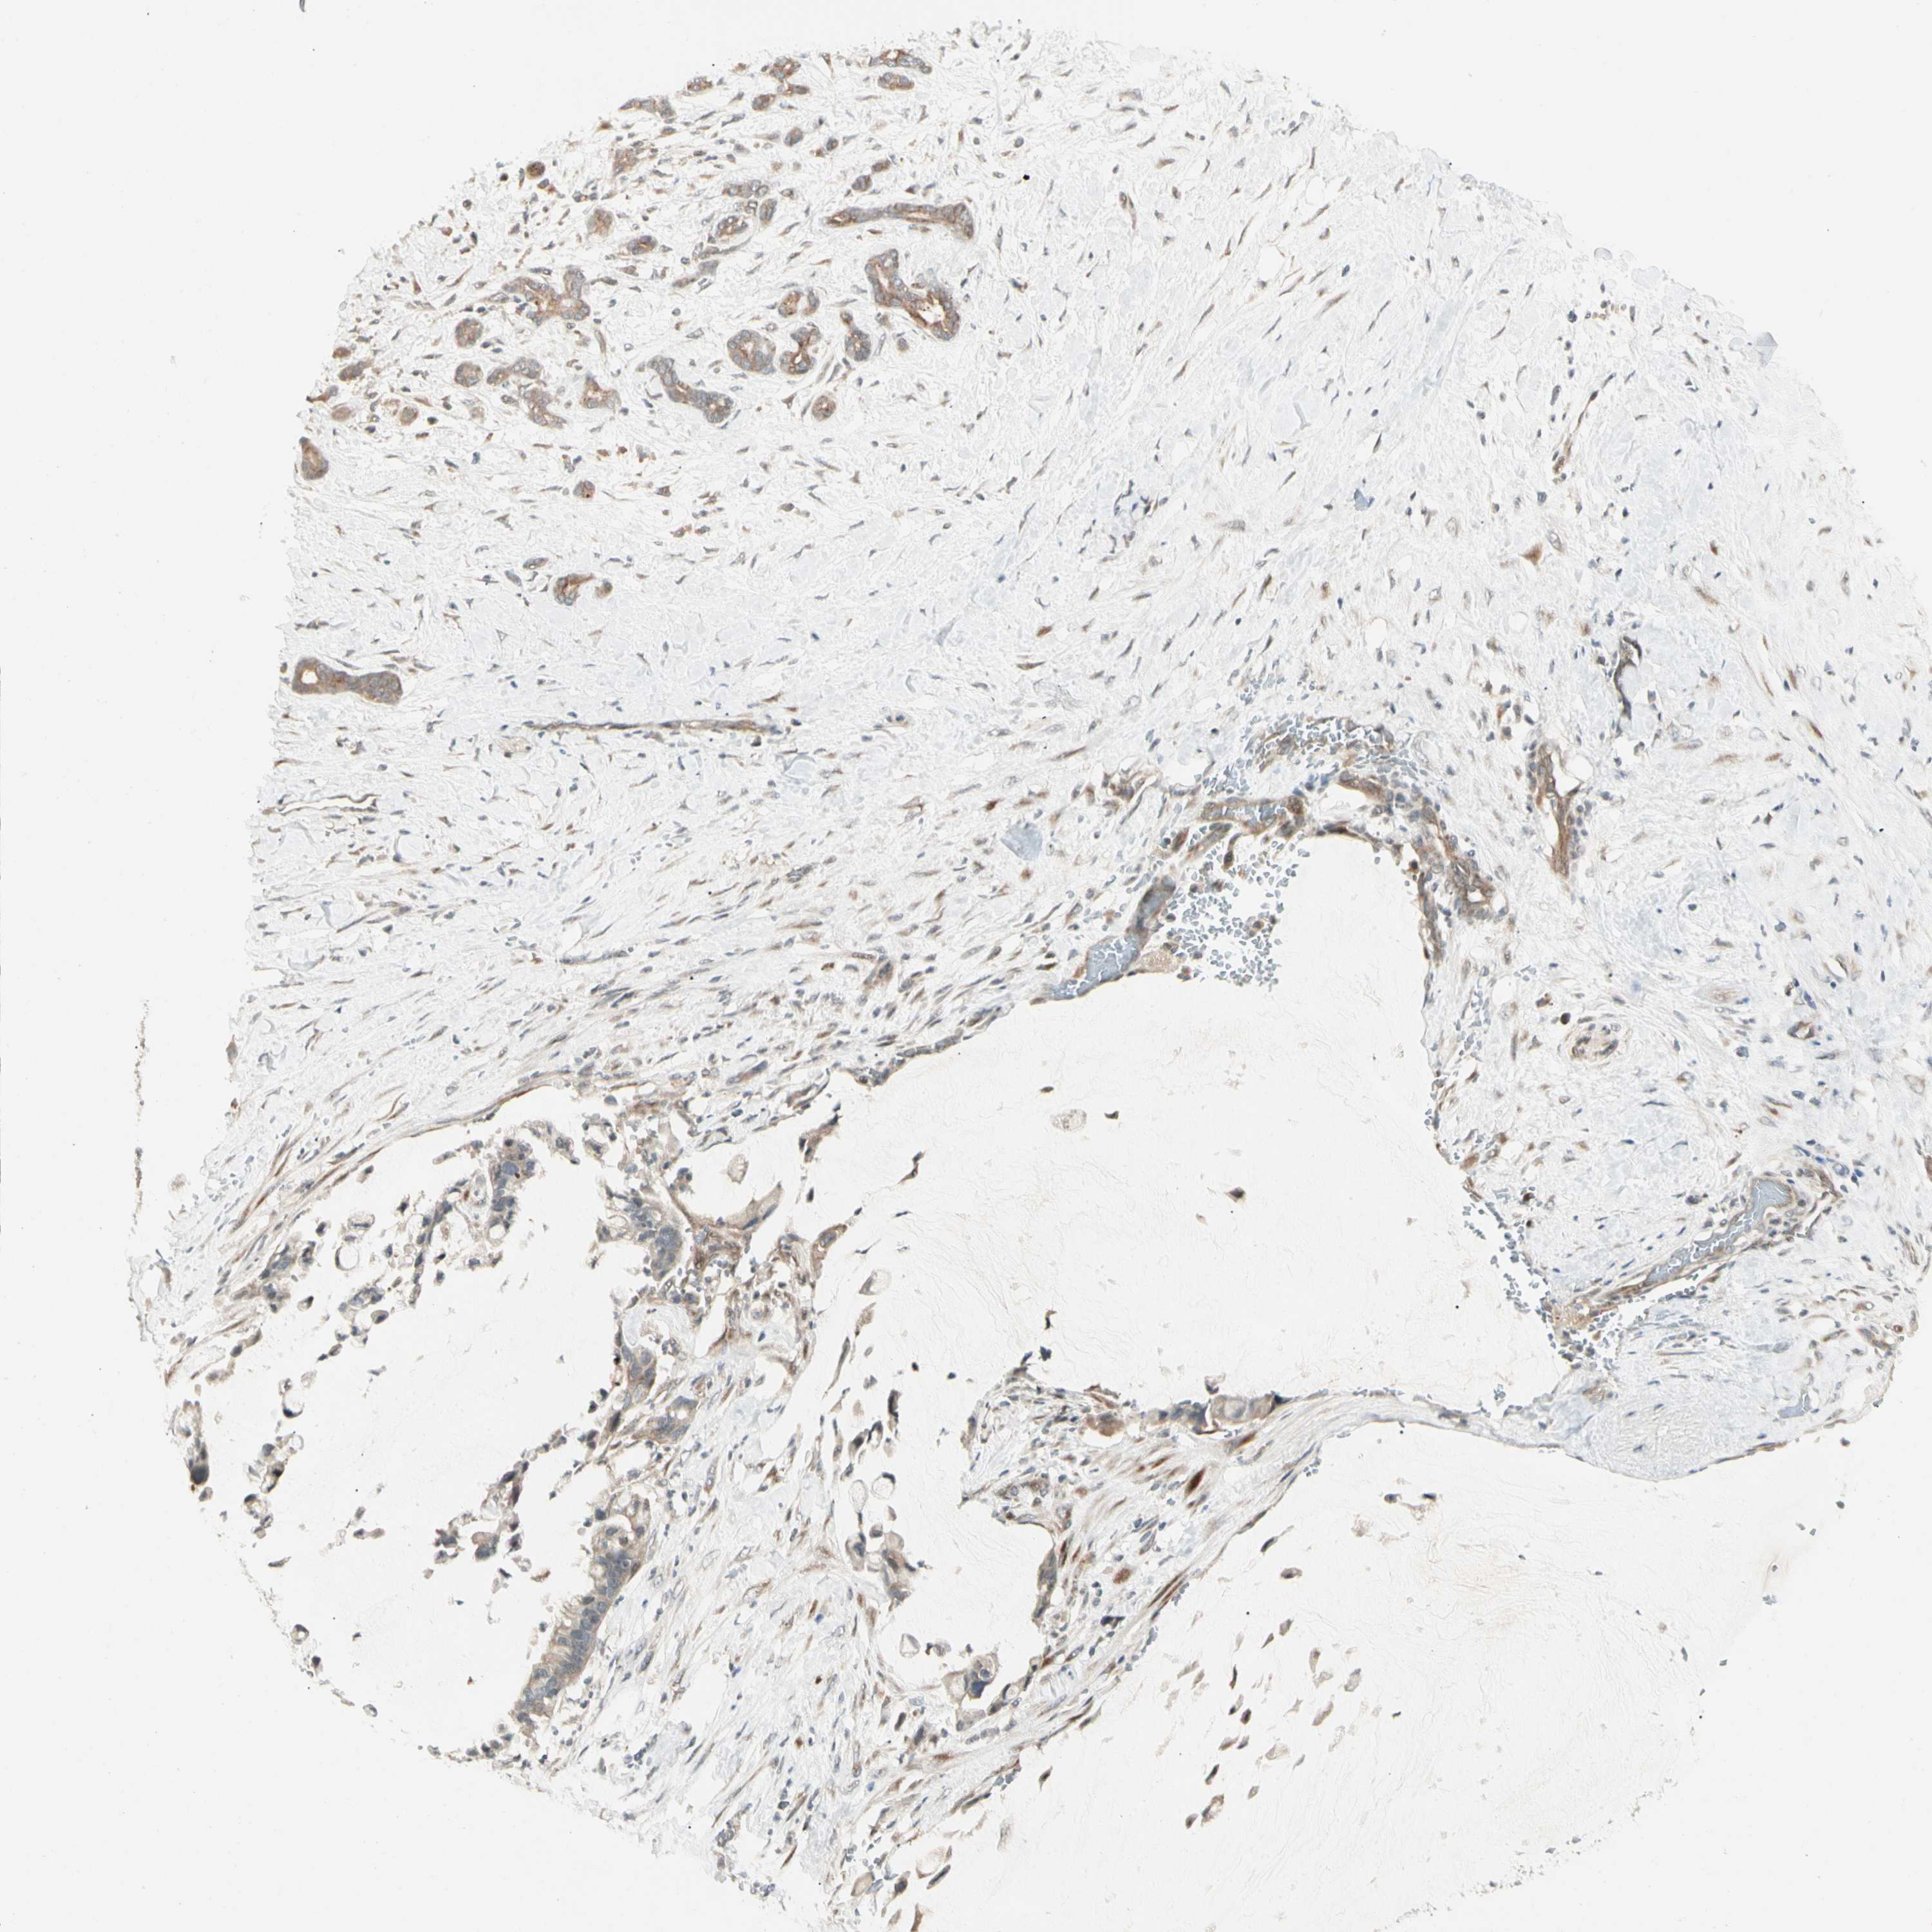

PANCREATIC CANCER - Protein expressioni

A mouse-over function shows sample information and annotation data. Click on an image to view it in a full screen mode. Samples can be filtered based on level of antibody staining by selecting one or several of the following categories: high, medium, low and not detected. The assay and annotation is described here.

Note that samples used for immunohistochemistry by the Human Protein Atlas do not correspond to samples in the TCGA dataset.

Antibody stainingi

Antibody staining in the annotated cell types in the current human tissue is reported as not detected, low, medium, or high, based on conventional immunohistochemistry profiling in selected tissues. This score is based on the combination of the staining intensity and fraction of stained cells.

Each image is clickable and will lead to virtual microscopy that enables deeper exploration of all samples and also displays staining intensity scores, fraction scores and subcellular localization as well as patient and tissue information for each sample.

Antibody HPA007859

Staining

High

Medium

Low

Not detected

Intensity

Strong

Moderate

Weak

Negative

Quantity

>75%

75%-25%

<25%

None

Location

Nuclear

Cytoplasmic/membranous

Cytoplasmic/membranous,nuclear

Adenocarcinoma, NOS